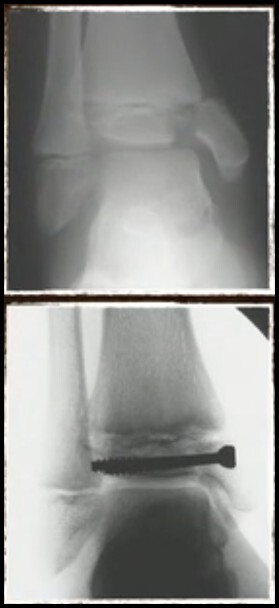

• Cirúrgico > 2 mm desvio

• 1% dos casos

• Supinação-Inversão

• Geralmente desviados

• RAFI via medial